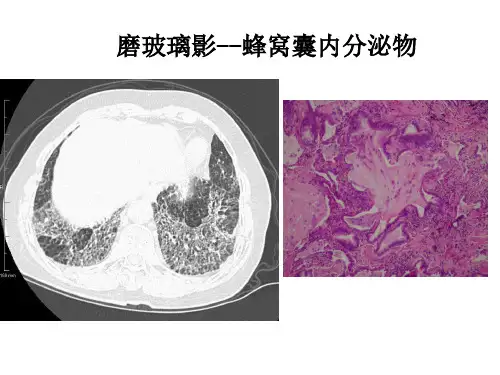

HRCT对特发性肺间质纤维化的鉴别诊断价值临床研究马磊【摘要】目的分析HRCT(高分辨率CT)对特发性肺间质纤维化的诊断价值.方法回顾收集经病理证实的56例特发性间质性肺炎患者影像学资料,患者均进行HRCT 扫描,根据扫描结果判断疾病分布,并分析不同时期的成像特点.结果 HRCT主要表现有磨玻璃样阴影改变、网状改变、蜂窝状改变、胸膜下间质纤维化等特点,本次56例患者中,46.4%为早期患者,HRCT图像表现为磨玻璃样、小叶内间质增厚、小叶间隔增厚表现;53.6%为非早期患者,除上述症状,还出现胸膜下弧线影及蜂窝肺,其中小叶间隔增厚所占比例最高.结论不同时期的特发性肺间质纤维化HRCT各有特点,其成像结果能有效反映病变情况,可用于特发性肺间质纤维化鉴别诊断.【期刊名称】《罕少疾病杂志》【年(卷),期】2019(026)002【总页数】3页(P41-42,45)【关键词】高分辨率CT;肺间质纤维化;诊断【作者】马磊【作者单位】河南省新乡市第二人民医院CT室,河南新乡453000【正文语种】中文【中图分类】R563.1+3特发性间质性肺炎(idiopathic interstitial pulmonary fibrosis,IPF)是一种广泛纤维性肺泡炎,主要以肺泡壁为主要病变引起的一种异质性组成的疾病谱,其病因尚未明确,目前认为与机体免疫系统功能紊乱有关[1]。

IPF的HRCT表现为基底部和外周部位的双肺弥漫间质性纤维化,伴有蜂窝样改变。

个别早期患者的胸片可能基本正常或呈磨玻璃样变化。

随着病情的进展,可出现直径多在3-15mm大小的多发性囊状透光影(蜂窝肺)。

HRCT 有利于发现早期病变,病灶以胸膜下、基底部为主;网格状异常改变;蜂窝肺伴或不伴牵张性支气管扩张。

UIP型的HRCT诊断标准:1、UIP型(满足所有4条标准):病灶以胸膜下、基底部为主;网格状异常改变;蜂窝肺伴或不伴牵张性支气管扩张;无不符合UIP型所列的特征。

3、不符合UIP型(七个特征中任何一个条件):病灶以中上肺为主;病灶以支气管血管束为主;广泛的毛玻璃样改变(范围超过网格状异常改变); 过多的微结节(双侧,上肺);不连续的囊腔(多发、双侧、远离蜂窝肺);弥漫性马赛克征/气体陷闭;支气管肺段/肺叶实变。